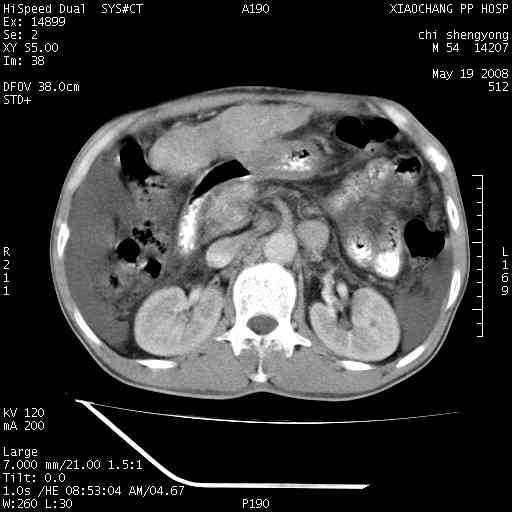

以下是引用zjzjr在2008-5-21 10:52:00的发言:[br]肝左叶巨块型肝癌伴门静脉左支瘤栓形成.肝硬化、腹水,胃底静脉曲张,脾术后改变。

以下是引用随光逐影在2008-5-21 16:20:00的发言:[br]1)肝左叶肝癌伴门静脉左支瘤栓形成,腹膜后淋巴结转移。2)肝硬化、腹水、胃底静脉曲张。3)胆囊炎。4)脾脏缺如,为切除术后所致。